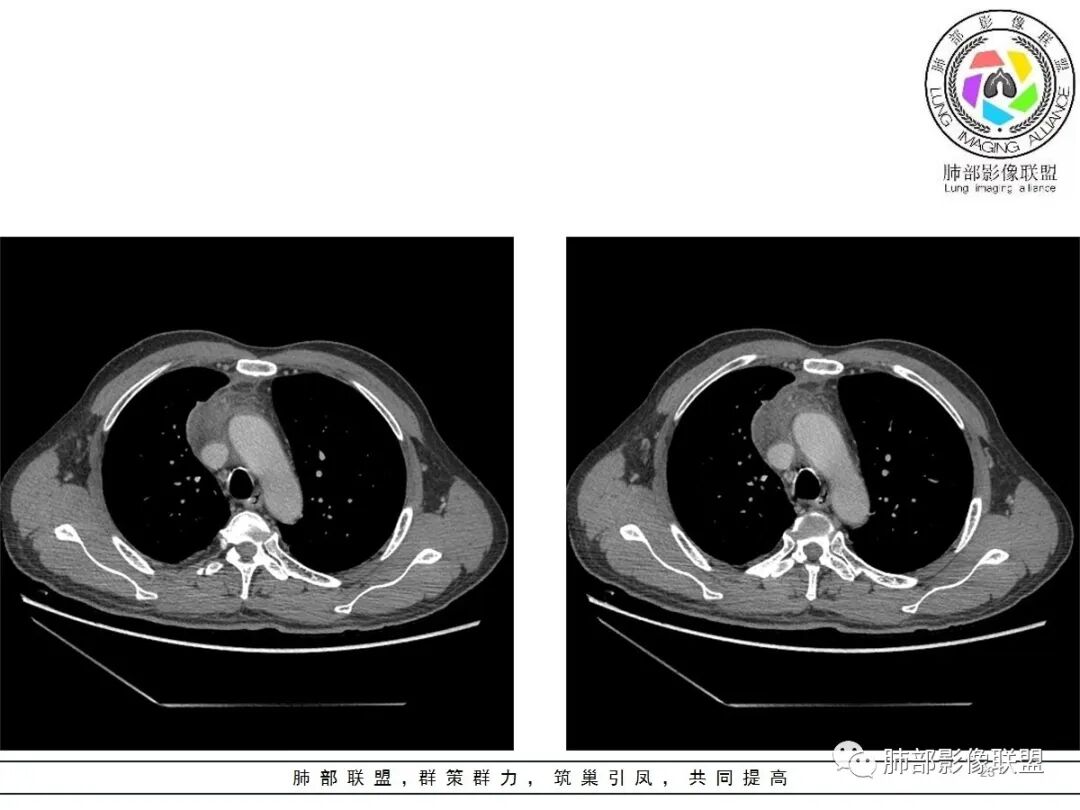

19日,4天后, 内部低密度影有,周围渗出增多,胸水增多

薄膜状强化

影像上周围病灶变化明显

常规肿瘤侵犯不支持,太快

应该是炎性病变渗出

脂肪密度明显,还有钙化、囊性病变,支持含脂质类病变破裂

周围是化学性炎症或出血所致

后期强化,可能与炎症有关

4.四天内病灶变化快,块影增大且不规则,包膜似不完整,边界不清,上份可见浸润或渗出,与周围心脏大血管及心包等间隙不清。胸水增多。

第一次的检查符合胸腺瘤影像学改变,短期内的形态学改变及突然出现的边界模糊或浸润等,符合出血或炎症。